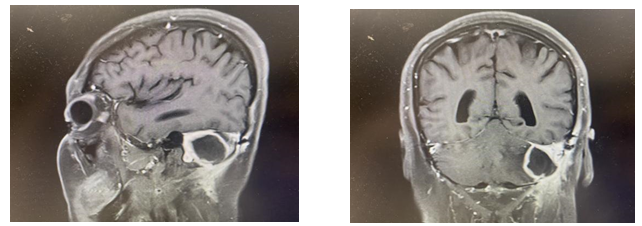

图:核磁提示脑脓肿形成

傅继弟教授查看患者后指出:患者既往有“脑膜瘤”手术史,术后生命体征平稳,术后一个月出现头晕、肢体麻木,核磁检查考虑颅内脓肿形成。患者术后至今无明显发热,无皮肤破溃及脓液渗出,入院后血常规白细胞及中性比无明显升高。患者出现意识状态下降及肢体麻木后,核磁见脓腔周围无明显水肿,急诊予以激素及甘露醇1天后,状态有明显好转。综合考虑患者病史及体征,考虑术中放置的人工材料刺激,导致无菌性炎症。脓肿形成后产生的占位效应压迫脑组织,导致头晕及肢体麻木。静脉应用甘露醇缓解高颅压症状,查无手术禁忌后择期手术清除脓腔。注意留取标本行细菌培养。